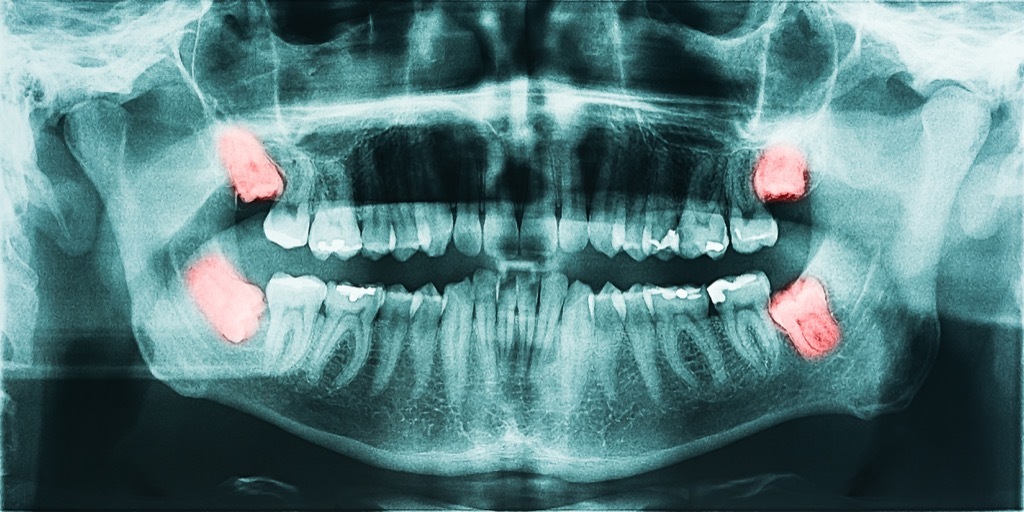

8 Ihre Weisheitszähne bleiben kann

Die überwiegende Mehrheit der Menschen haben ihre Weisheitszähne früh auf Empfehlung von ihrem Zahnärzte im Leben gezogen, der unnachgiebig ist, dass sie auch problematisch werden, wenn sie jetzt nicht richtig sind. Von denen, die wählen, die meisten finden, zu warten, bis es zu einem Problem wird, dass sie ihr ganzes Leben leben könnenohne Probleme aus ihren Weisheitszähnen.